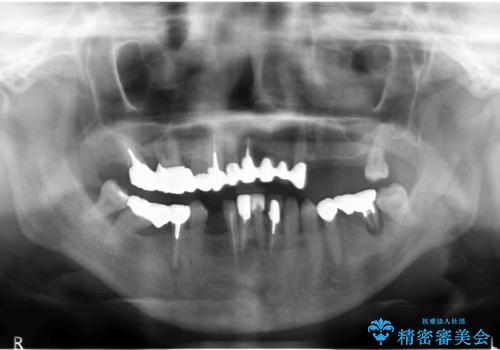

歯周病 全顎治療

- 前歯の見た目、入れ歯による噛めないことの改善を求めて来院されました。

検査により全顎的な歯周病治療、欠損のインプラント補綴、根管治療が必要な状態であることをお伝えし、治療を計画します。

全体的な歯周病が認められる場合、歯を失った一部のみの治療となることはほぼありません。

失ってしまった機能を回復し、今後歯を失わないよう残せる歯に歯周病治療を行い、安定した咬合を確立することで長期的に問題なく噛めるような口腔内環境を達成できるようになると考えます。